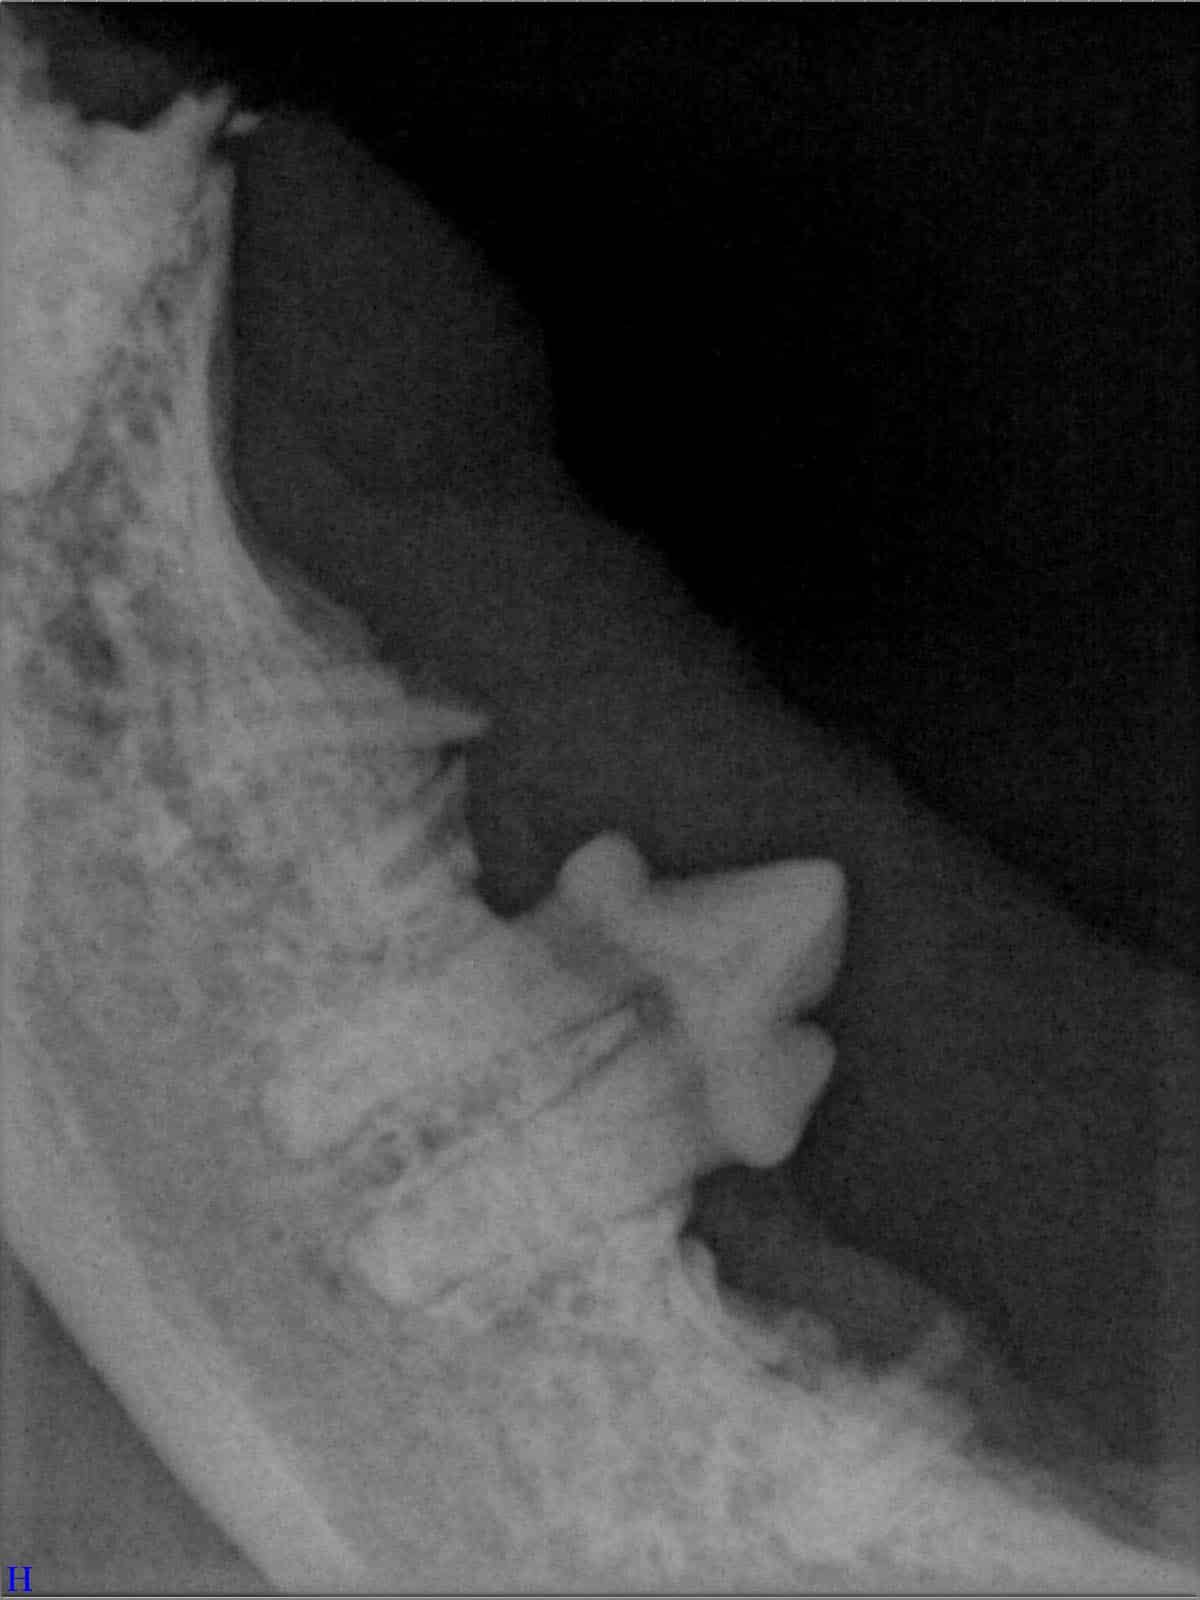

Ein entscheidender Baustein der FORL-Diagnostik ist das dentale Röntgen. Viele Läsionen sind von außen nicht sichtbar und lassen sich ausschließlich mithilfe moderner Röntgentechnik erkennen. In der Hamburger Praxis kommt digitales Dentalröntgen zum Einsatz, das detailreiche Aufnahmen bei geringer Strahlenbelastung ermöglicht. So kann FORL bereits in frühen Stadien diagnostiziert werden.

Das sehen Sie von außen – so sieht es auf den Röntgenbildern aus.

FORL Katze Röntgenbild

Röntgenbilder